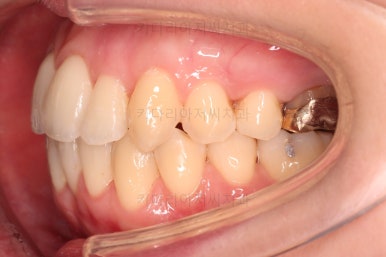

초진 시, 입안의 모습입니다.

좌측 송곳니가 덧니처럼 튀어나가 있고, 송곳니 옆의 작은 억므니가 안으로 쏙 들어가서 덧니 느낌이 더 강조되어 보이네요.

위아래 앞니가 긴밀하게 겹침이 없는 약간의 개방교합(오픈바이트, Openbite) 경향이 보입니다.

웃거나 말할 때 드러나는 치열이 삐뚤어서 심미적으로 좋지 못하고요.